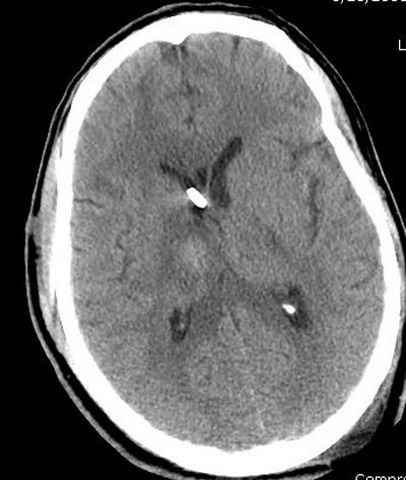

Наблюдается службой травмы и нейрохирургии (ICP) Increased Intracranial Pressure by ventricular cateter

монииторинг

-Согласен, рана до прихода пластического хирурга была 38х13 см, можно было постараться закрыть сверху, а в нижнем отделе где был ожог, применить кожную пластику меньшим размером. К моему удивлению и разочарованию, когда вернулся из другой операционной (шли пареллельные операции), он уже успешно заканчивал свое дело. Кстати недавно разговаривал с нейрохирургом, он снял ICP (intracranial prеssure monitor), внутричерепное давление стабилизировалось, ортопеды и хирурги закончили с лечением, теперь длительное неврологическое восстановление.